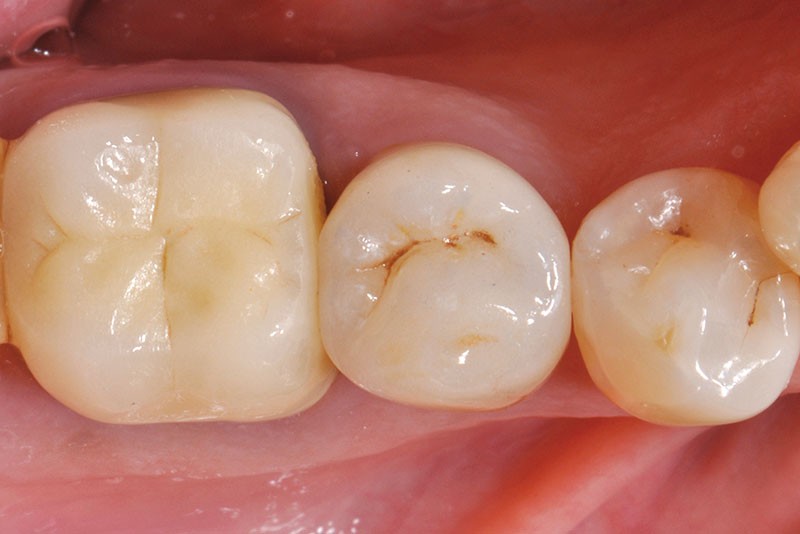

34, 35. Vues vestibulaire et occlusale de la prothèse d’usage collée sur 45 (Laboratoire du Sud-Ouest).